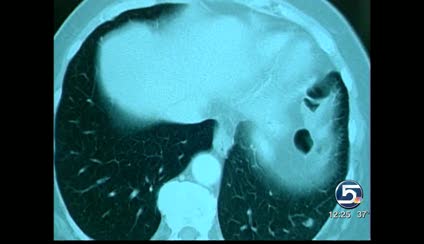

"I found from the X-rays that my shoulder was really fine, but I had a mass in my lung," she says.

The mass was stage-four lung cancer, which had spread to her clavicle. The cause was baffling.

Egan had the more common gene mutation and took the targeted drug as part of a clinical trial. Within nine weeks her lung tumor shrunk by 80 percent. She took the medicine for a year and a half. Then her tumor began to change and Dr. Akerley recommended she begin chemotherapy. She has had three rounds of chemo but still feels healthy and keeps a positive attitude.